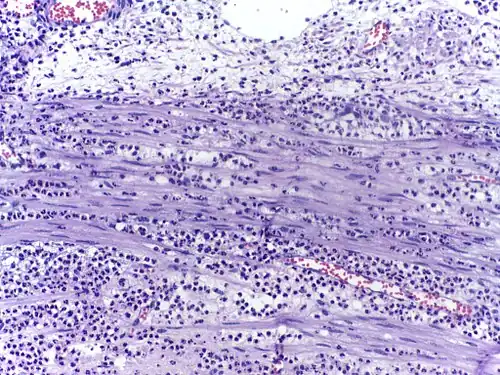

Воспалённые или повреждённые участки соединительной ткани требуют немедленной миграции разнообразных лейкоцитов, в том числе нейтрофилов, в очаг повреждения для удаления патогенных микроорганизмов и восстановления ткани. Наиболее хорошо процесс миграции в ткани изучен для нейтрофилов, которые прибывают в очаг воспаления первыми, существенно быстрее моноцитов, и способны развивать защитные метаболические реакции (в частности, «окислительный взрыв», сопровождающийся продукцией активных форм кислорода) в течение секунд. Активация нейтрофилов сопровождается в первую очередь высвобождением содержимого секреторных гранул. При развитии локального воспаления макрофаги, активированные бактериями или повреждениями ткани, выделяют провоспалительные цитокины, такие как IL-1 или фактор некроза опухоли α (TNF-α). Также к факторам хемотаксиса нейтрофилов относят компоненты комплемента, вещества, выделяемые тучными клетками, иммунные комплексы, эндотоксины и бактериальные пептиды, а также наполненные лизосомы, выходящие в ткань при распаде погибших нейтрофилов и макрофагов[33]. Под действием провоспалительных цитокинов в эндотелиальных клетках, выстилающих ближайшие к очагу воспаления посткапиллярные венулы, увеличивается количество селектинов на поверхности, обращённой в просвет сосуда. Нейтрофилы, циркулирующие в посткапиллярных венулах и имеющие подходящий набор поверхностных гликопротеинов, связываются с селектинами на поверхности эндотелиальных клеток. На данном этапе связывание с эндотелием непрочное, и нейтрофилы продолжают «катиться» по поверхности эндотелия. Провоспалительные цитокины запускают экспрессию интегринов в катящихся нейтрофилах и лигандов интегринов, известных как ICAM-1, на поверхностях эндотелиальных клеток. В то же время межклеточные контакты между клетками эндотелия ослабляются, и эндотелий становится более проницаемым. За счёт интегринов нейтрофилы прочно связываются с эндотелием и прекращают качение, и в конечном счёте приступают к прохождению через эндотелий с помощью псевдоподий (этот процесс известен как диапедез). Проникновение нейтрофилов через эндотелий облегчается благодаря длинному и сегментированному ядру. Прохождение нейтрофилов через эндотелий и дальнейшая миграция к очагу воспаления стимулируются хемокинами[34]. Базальные мембраны нейтрофилы преодолевают благодаря выделению содержимого желатиназных гранул[35].

Нейтрофилы являются основными фагоцитами кровотока, но в ходе острого воспаления интенсивно мигрируют в очаг воспаления[8][9][10]. Они проникают через стенки кровеносных сосудов и движутся по градиенту различных провоспалительных молекул в ходе хемотаксиса[11]. Нейтрофилы — самые многочисленные клетки, входящие в состав гноя, именно они придают ему беловатый или желтоватый цвет[12].